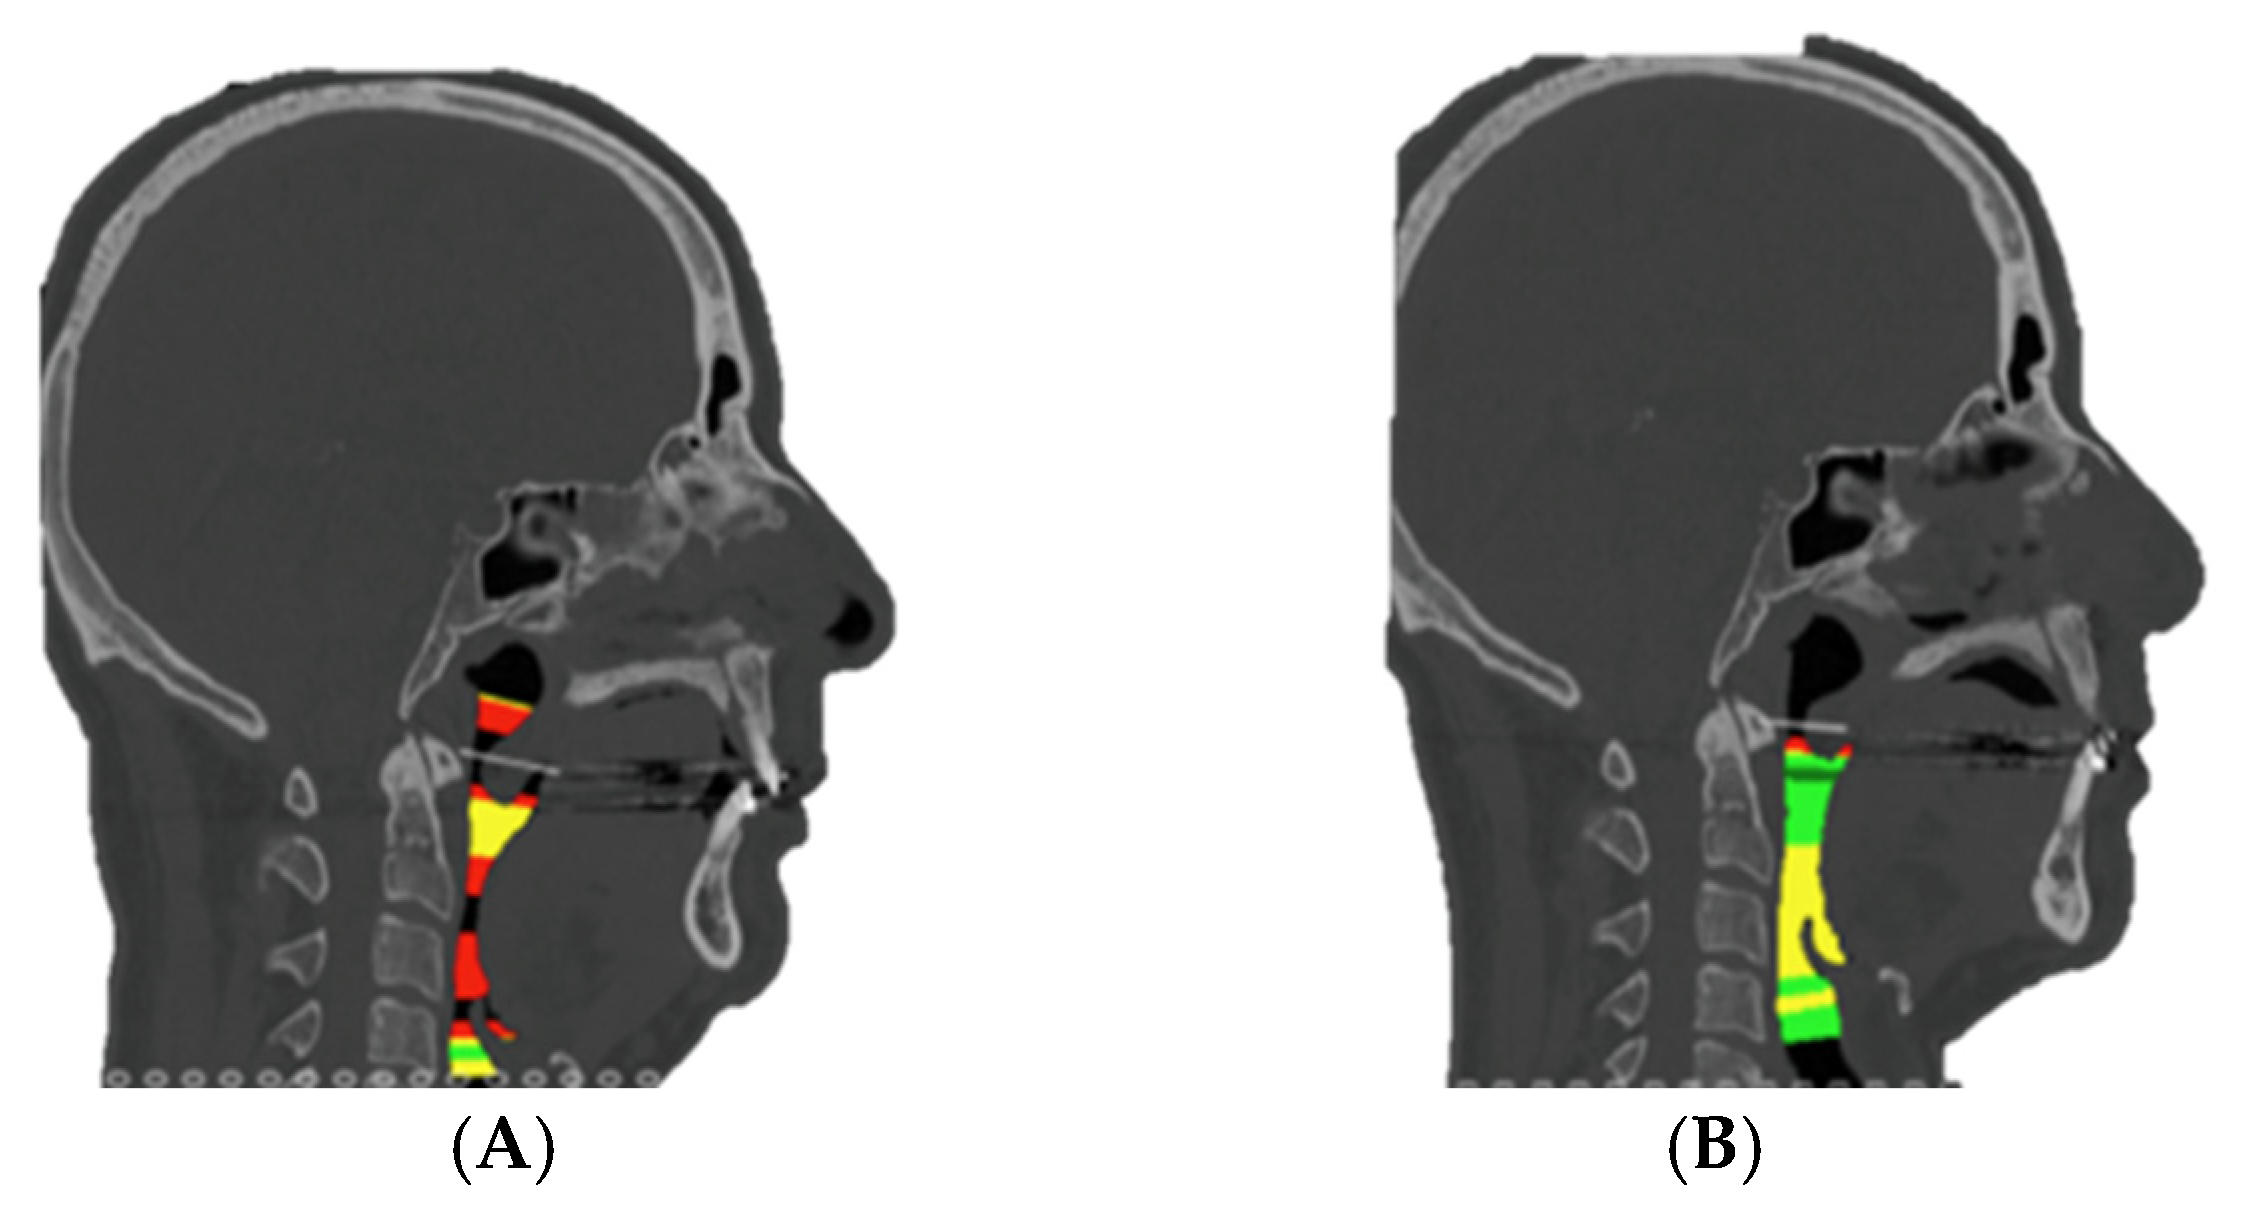

Prior to surgery, helical CT scans were performed with the following parameters: 0.625 mm slice thickness, voxel size of 0.5 × 0.5 × 0.625 mm, 120 kVp, and 200 mA. Head and neck scans were acquired in natural head position with the patient in supine position. These scans, along with occlusal records obtained through digital models and clinical photographs of the patient, were integrated into the Dolphin Imaging surgical planning software version 11.95®. Using these records, a 3D reconstruction of the patient’s skull was created, aligned with its natural head position. The Le Fort and BSSO osteotomies were then designed. The planned movements of the maxilla and mandible were virtually simulated (Figure 1), and an intermediate and final splint were designed for a maxilla-first sequence treatment, which were then 3D printed.

Figure 1. Step 1. The green mandible represents the preoperative mandibular position. The blue mandible ilustrates the postoperative (planned) position of the distal mandibular segment following virtual repositioning The yelow structures correspond to the cranial base and proximal mandibular segments, serving as stable reference points during simulation. The white maxilla and dentition are shown as unchanged anatomical references, used to guide occlusion and evaluate surgical accuracy.